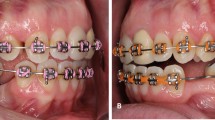

All MIs were inserted under local anesthesia by one orthodontist (RH) without mucoperiosteal incision or flap, at the level of the attached gingival line, using a manual self-drilling method. The insertion angulation was at 30–35° to the horizontal. Based on clinical judgment in the individual situations, 4 placement sites were selected: (1) between canines and first premolars (C-Pm1), (2) between first and second premolars (Pm1–Pm2), (3) between second premolars and permanent first molars (Pm2-M1), and (4) between first and second permanent molars (M1–M2). Periapical radiographs were taken before and after MI placement with the orthoradial-projection technique using an X-ray holder (Rinn, Dentsply, USA) and a digital radiographic machine (Instrumentarium Dental Company, Tuusula, Finland). After confirming initial stability, the MIs were immediately loaded with a power chain (around 150 g). The implantation was considered successful when the MI remained stable throughout force application, until completion of the required orthodontic movement. Failure was recorded at the time of observation in the mouth.

The radiographs were processed using the manufacturer’s program (Cliniview Software, Version 9.3.0.6); their ratios to actual size were 1:1. The following measurements were recorded (Fig.1):

Perpendicular distance from the MI tip to the root of the most adjacent tooth (DT); the perpendicular was projected to the long axis of the adjacent root.

Perpendicular distance from the MI tip to the alveolar crestal bone level (DC); the perpendicular was projected to the tangent to the alveolar crestal tip. The shortest distance to either the mesial or distal root was considered in the statistical computations.

The radiographic measurements were performed blindly, without knowledge of MI failure. To evaluate the error of magnification, we measured the height and width of the premolar bracket on 20 randomly selected radiographs, as well as the length of 20 MIs on another 20 randomly selected radiographs. The brackets and MIs were compared with the actual standard height (3.0 mm) and width (3.1 mm) of the bracket and the length of the MI (8 mm for both types). The average magnification for bracket height and width were 0.015 + 0.06 mm and 0.01 + 0.06 mm, respectively. The magnification for the MI was 0.1 ± 0.09 mm. Accordingly, the direct measurements on radiographs were adopted for statistical computations.

The clinical implication would be to insert the screw away from the crestal edge at a level where a thicker layer of bone would account for the observed stability. Combining this directive with the indication to position the MI within the attached keratinized gingiva for stability and long-term maintenance without inflammation [9, 19, 20], an optimal apical angulation of the MIs (30–35° to the horizontal) would be warranted. Although such an angulation has been proposed to avoid root damage during placement [25, 26], our findings suggest that it would also be essential to maximize MI stability. Further research focused on this aspect is indicated.